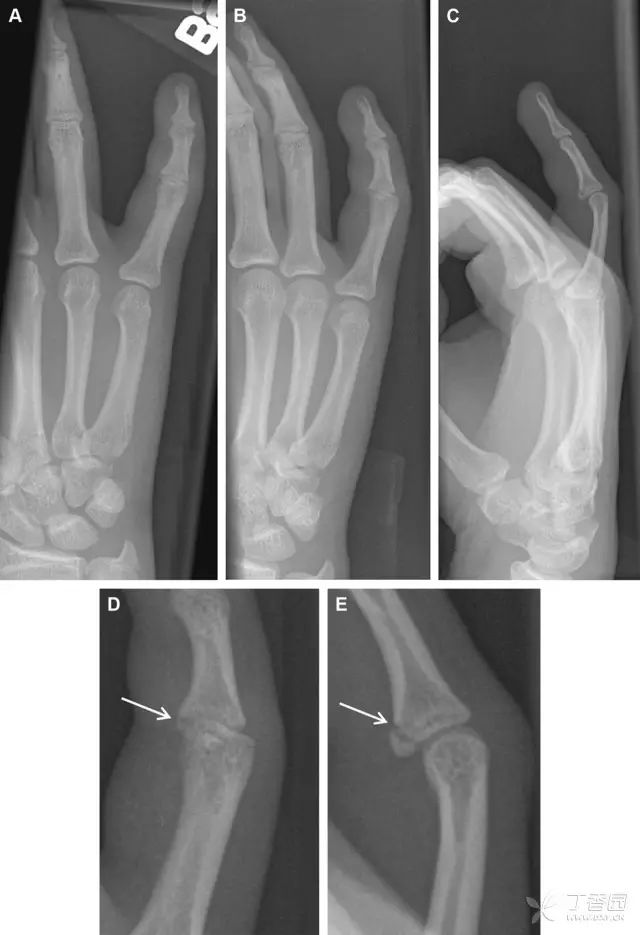

常规进行前后位、侧位、斜位 X 线检查,对于大多数桡骨远端骨折来说不容易漏诊;但是对于无移位的骨折,特别是桡骨茎突骨折,容易漏诊。桡骨茎突骨折是一斜行的骨折,常累及关节面,常发生于轴向应力或直接打击。

图 1 57 岁女性,摔倒后手掌撑地,桡骨茎突压痛。(A~C)前后位、斜位、侧位片示软组织肿胀(*)和发丝样骨折(白色箭头);(D~F)2 周后,前后位、斜位、侧位片示骨折线显明,由于新骨痂沉积而呈现透亮线与硬化线并存;(G~I)另一患者,桡骨茎突骨折在前后位及侧位片上显示不明显,而在斜位片显示更清楚

舟状骨骨折 60%~70% 发生于腰部,15% 发生于近极, 10% 发生于远极, 8% 发生于远端关节面。除了常规的前后位、侧位、斜位片外,还需要拍专门的舟状骨位片(腕关节尺偏,以舟状骨为中心的腕关节前后位片),特别是鼻烟壶有压痛时。

图 2 舟状骨骨折 (A、B)第 1 例患者,舟状骨远极关节内骨折(白色箭头),斜位片显示较清楚(B);(C、D)第 2 例患者,舟状骨腰部骨折(虚线箭头),斜位片显示较清楚(D);(E~H)第 3 例患者,舟状骨近极骨折,常规 X 线片均未看到骨折,而在舟状骨位片上才能见到骨折(虚线圆)

掌板是掌指关节和指间关节关节囊掌侧的纤维结构,防止关节过伸。掌板的远端部是增厚的纤维软骨,附着于指骨掌侧基底部,而其两侧与侧副韧带的纤维融合。掌板骨折多发生于过伸损伤,为撕脱性骨折。

图 3 掌板骨折(A~C)小指前后位、斜位、侧位片,由于骨折的部位及特点,在前后位片上通常难以发现骨折;放大后的斜位(D)、侧位(E)可见一骨碎片(白色箭头)

腕掌关节骨折脱位为高能量损伤,常伴有神经损伤。腕掌关节组成骨多,侧位片上重叠遮挡多,骨折不易发现,容易漏诊。在前后位片上,关节面不平滑、关节间隙不对称、关节皮质破坏、关节面重叠常提示腕掌关节骨折脱位。特别是第 4、5 腕掌关节脱位,在前后位片上不容易发现;该损伤不稳定,也称为「变异型拳击手损伤/骨折」。

图 4 第 4、5 腕掌关节骨折脱位。(A)正常腕掌关节,关节面平衡起伏、平行;前后位(B)、斜位(C)、侧位(D),第 5 掌骨近端附近软组织肿胀(白色箭头),冠状面关节面重叠,背侧撞击剪切应力致钩状骨骨折(*),在前后位及斜位片上可见双密度影。第 4 掌骨底部可见微小骨折碎片(D,虚线箭头),第 4、5 掌骨掌侧成角。(E~G)变异型拳击手损伤:第 4、5 掌骨背侧脱位而未见骨折(E,虚线方框),钩状骨有骨折小碎片(F,短虚线箭头),第 4 掌骨基底部关节内骨折(G,长虚线箭头)

钩状骨骨折可发生于体部和钩部,钩部骨折更多见,可合并有第 4、5 腕掌关节脱位。受伤机制由直接暴力或腕横韧带撕脱伤所致。骨折征象包括钩部无显示、骨皮质边缘模糊、硬化或双密度影等。常规的正侧位常无法明确诊断,需要加拍腕管位,可清晰显示其钩部。

图 5 打高尔夫球后腕部急性疼痛。常规腕关节 X 线片正常(X)。腕管位片(B)隐约可见钩部横行骨折(虚线箭头),CT 检查(C、D)进一步明确了诊断

三角骨骨折是除舟状骨骨折外腕关节常见的骨折之一。其背侧是背侧桡腕韧带的附着点,因此背侧骨折更常见。常规正侧位片基本可明确诊断。背侧骨折可在侧位片上看到一小骨块。

图 6 三角骨骨折。(A)前后位片骨折不明显,(B)仅在侧位片上见一小骨块(短箭头),伴有软组织肿胀(长箭头)。